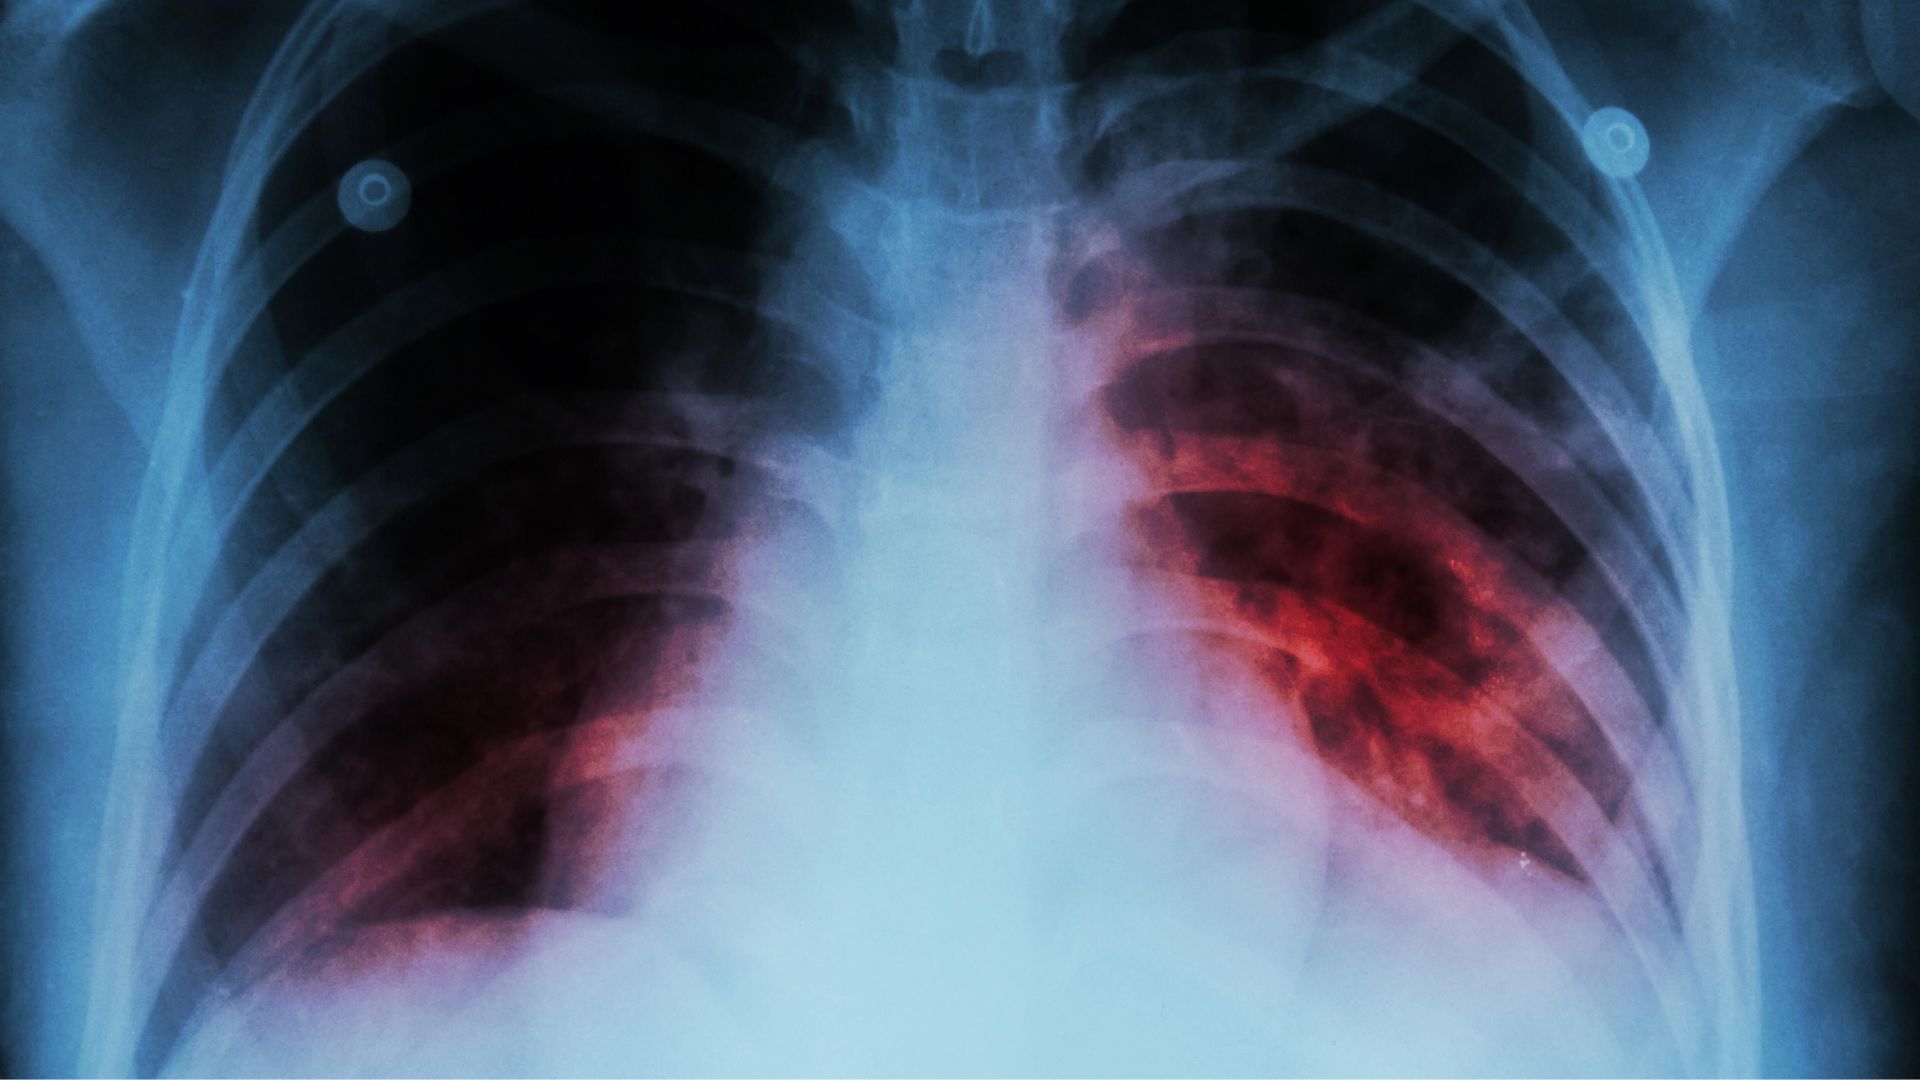

El investigador de El Colegio de la Frontera Sur (Ecosur), y presidente de la Red Mexicana de Investigación en Tuberculosis y Otras Micobacteriosis A.C, Héctor Javier Sánchez Pérez, alertó por el alarmante repunte de casos y muertes por tuberculosis en diferentes regiones de México.

A través de un comunicado, el académico explico que, tras la pandemia de covid-19, la tuberculosis recuperó fuerza y dejó cifras que no se veían desde hace años. El aumento de decesos y la presencia de micobacterias distintas a la tuberculosis son algunos de los signos que más preocupan.

Pérez estima que, solo en México, más de 3,000 personas mueren cada año por esta enfermedad. Cabe señalar que, en el mundo, alrededor de 10 millones de personas se contagian anualmente y más de un millón pierde la vida a causa de este letal agente infeccioso.

Foto: Medline Plus